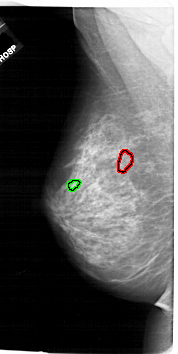

FILE: A_1744_1.LEFT_MLO.OVERLAY

TOTAL_ABNORMALITIES 1

ABNORMALITY 1

LESION_TYPE CALCIFICATION TYPE PLEOMORPHIC DISTRIBUTION CLUSTERED

ASSESSMENT 4

SUBTLETY 2

PATHOLOGY BENIGN

TOTAL_OUTLINES 1

BOUNDARY

ABNORMALITY 2